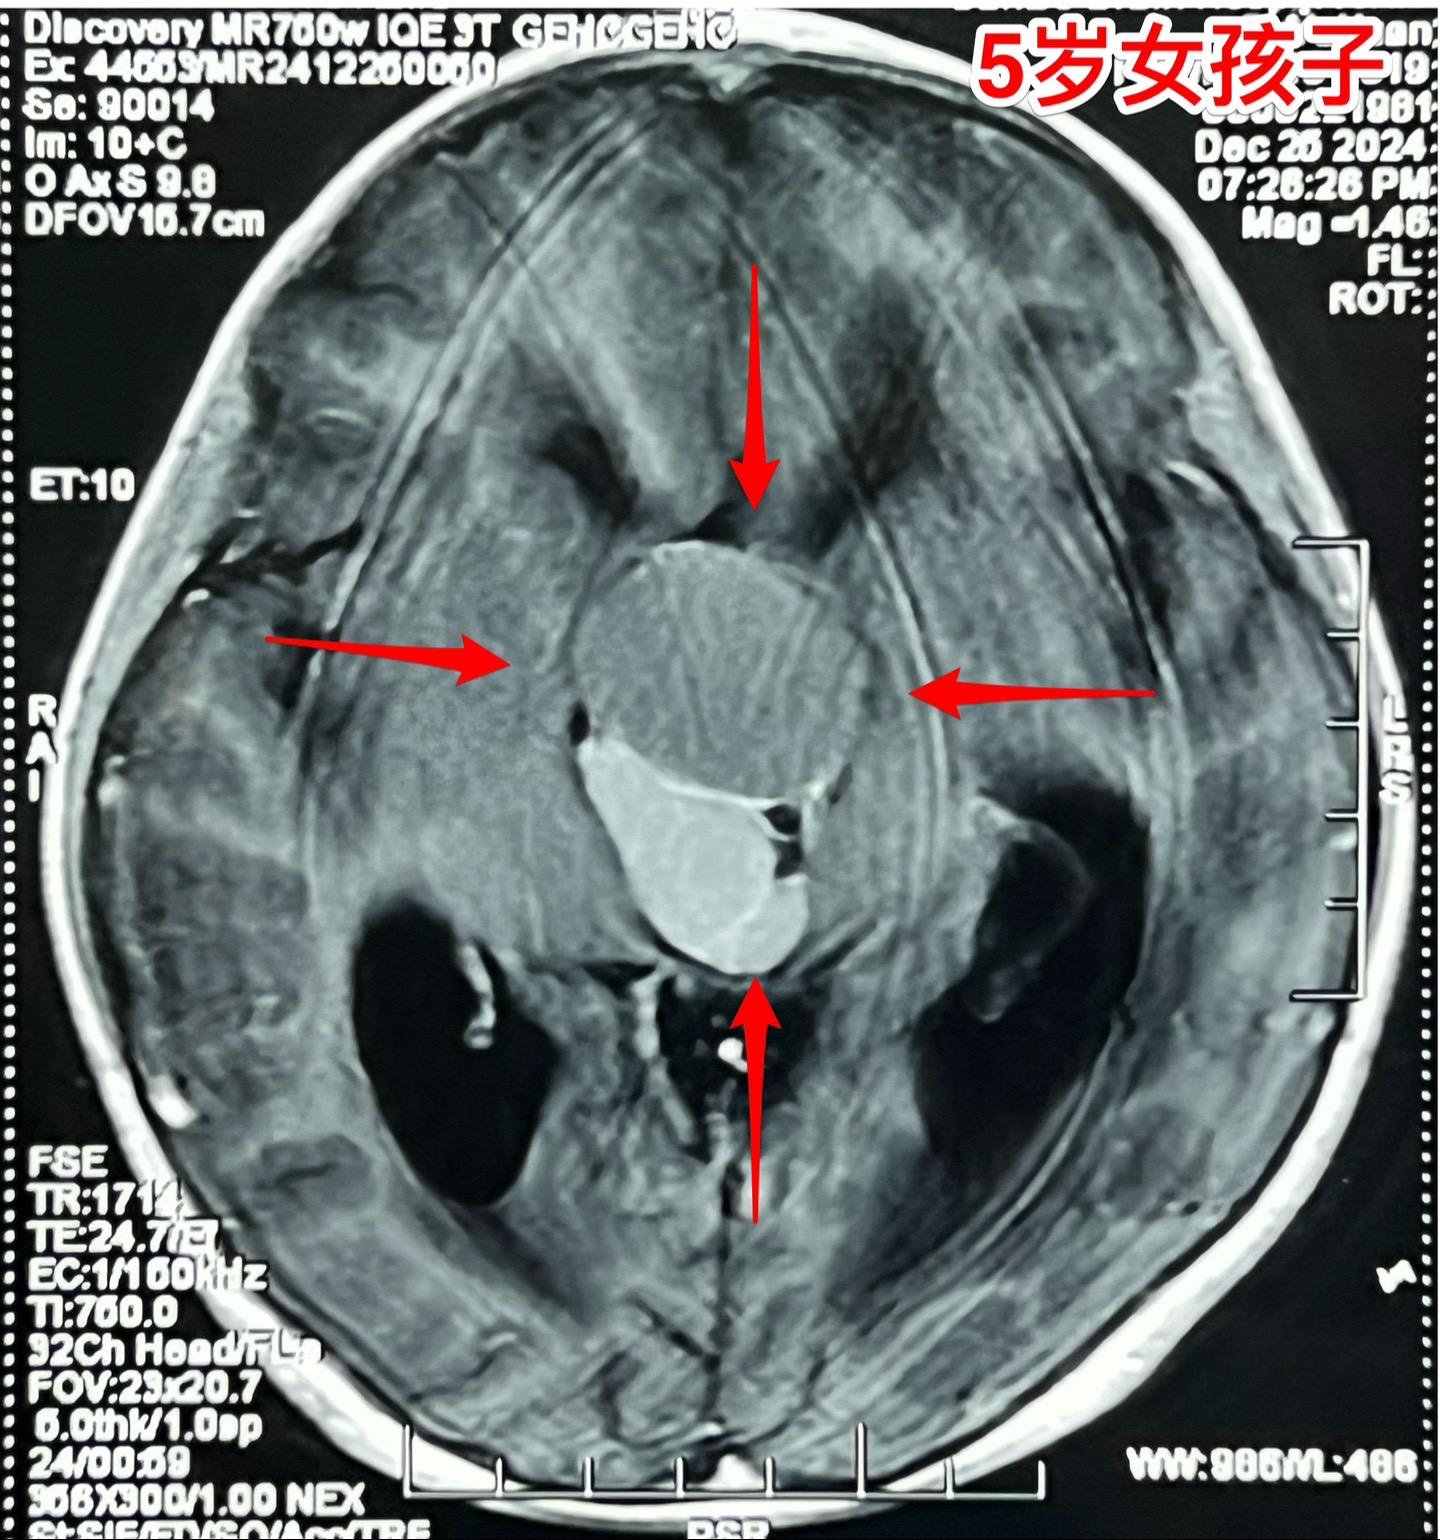

五岁商丘女孩颅咽管瘤像鸡蛋大。女孩子因为反复头痛、呕吐起病,一开始怀疑是胃肠炎,治疗后效果不好。于2024年12月18日作脑部磁共振和CT发现脑部肿瘤,怀疑是颅咽管瘤,孩子的妈妈和我加了,说肿瘤像鸡蛋那么大,焦急万分。 小孩子几经周折,最终到三博脑科医院找我办理住院手续。刚刚住院后又患感冒,发烧、咳嗽。感冒治好之后才于2025月1月7日作了手术。手术很顺利。 这个肿瘤体积大,导致脑积水,主体位于第三脑室内。对于我们科来说,这样的手术还不算是最难的。 希望小